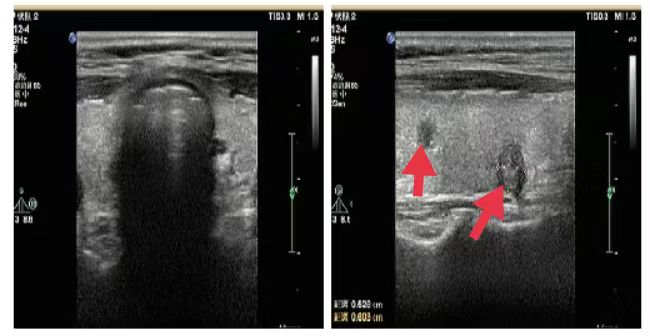

04、**女士,59岁

于2023年10月13日在邯郸仁泰北区体检,甲状腺彩超提示: 甲状腺切面形态大小正常,右叶实质内见2个低回声,较大约0.5cm*0.6cm,边界尚清,内见强回声,纵横比>1,CDFI:其内及周边未见血流信号。诊断:甲状腺结节伴钙化。建议客户到三甲医院进一步检查。2023年10月17日跟踪回访,客户告知,在邯郸某三甲医院穿刺确诊,甲状腺癌,准备手术。